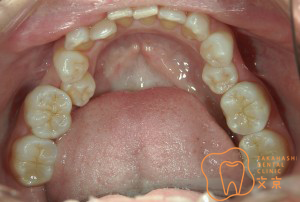

■奥歯でのつめもの治療 歯に優しい精密審美治療・精密歯科治療